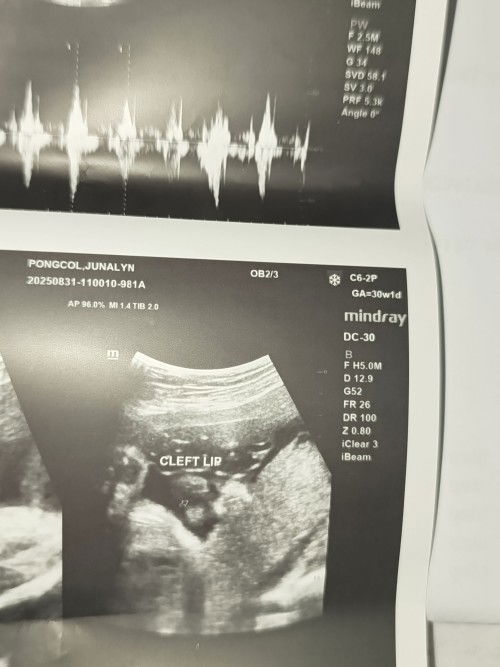

Cleft lip

Hi mga mamsh, may chance po bang magkamali yung ultrasound report ni baby? Based on ultrasound po kasi cleft lip siya. Im 24 weeks and 5 days pregnant po. Thanks in advance.

May cleft lip po ba talaga baby ko mga mhie🥺?